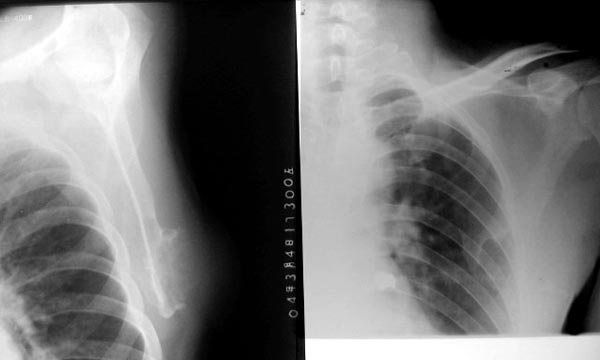

以下是引用lkc8963在2006-3-20 0:01:00的发言:[br]骨软骨瘤基本可定,至于有没有恶性变,本例依据不足,似见软块但皮下脂肪尚清,不知临床表现倒底有没有肿块还是突起?建议ct或穿刺检查。